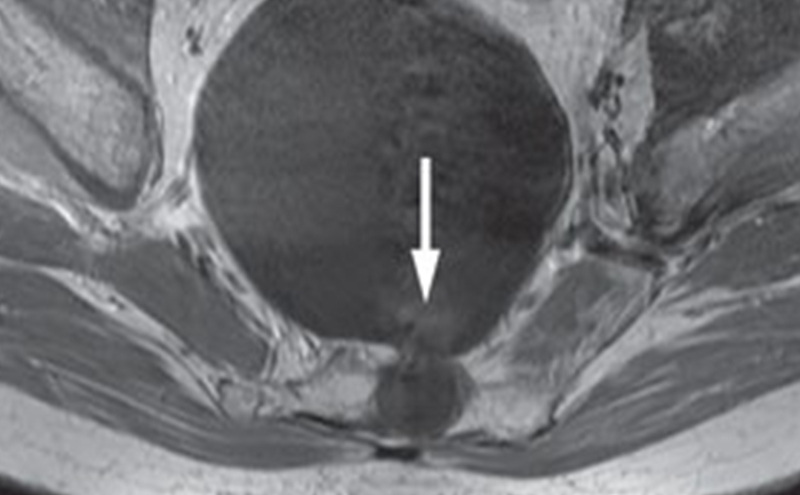

Under normal conditions, cells utilize oxidative phosphorylation to create ATP since it the most efficient form of energy production. Hydrogen ions are pumped into the intermembrane space as electrons flow through the electron transport chain. This creates an electrical gradient that allows H+ to flow back into the inner mitochondrial membrane through

ATP synthase, creating ATP.

In salicylate overdose, a higher percentage of salicylate is able to enter the cell. Since salicylates are weak acids, they steal the H+ created in the electron transport chain and ATP can’t be created.3